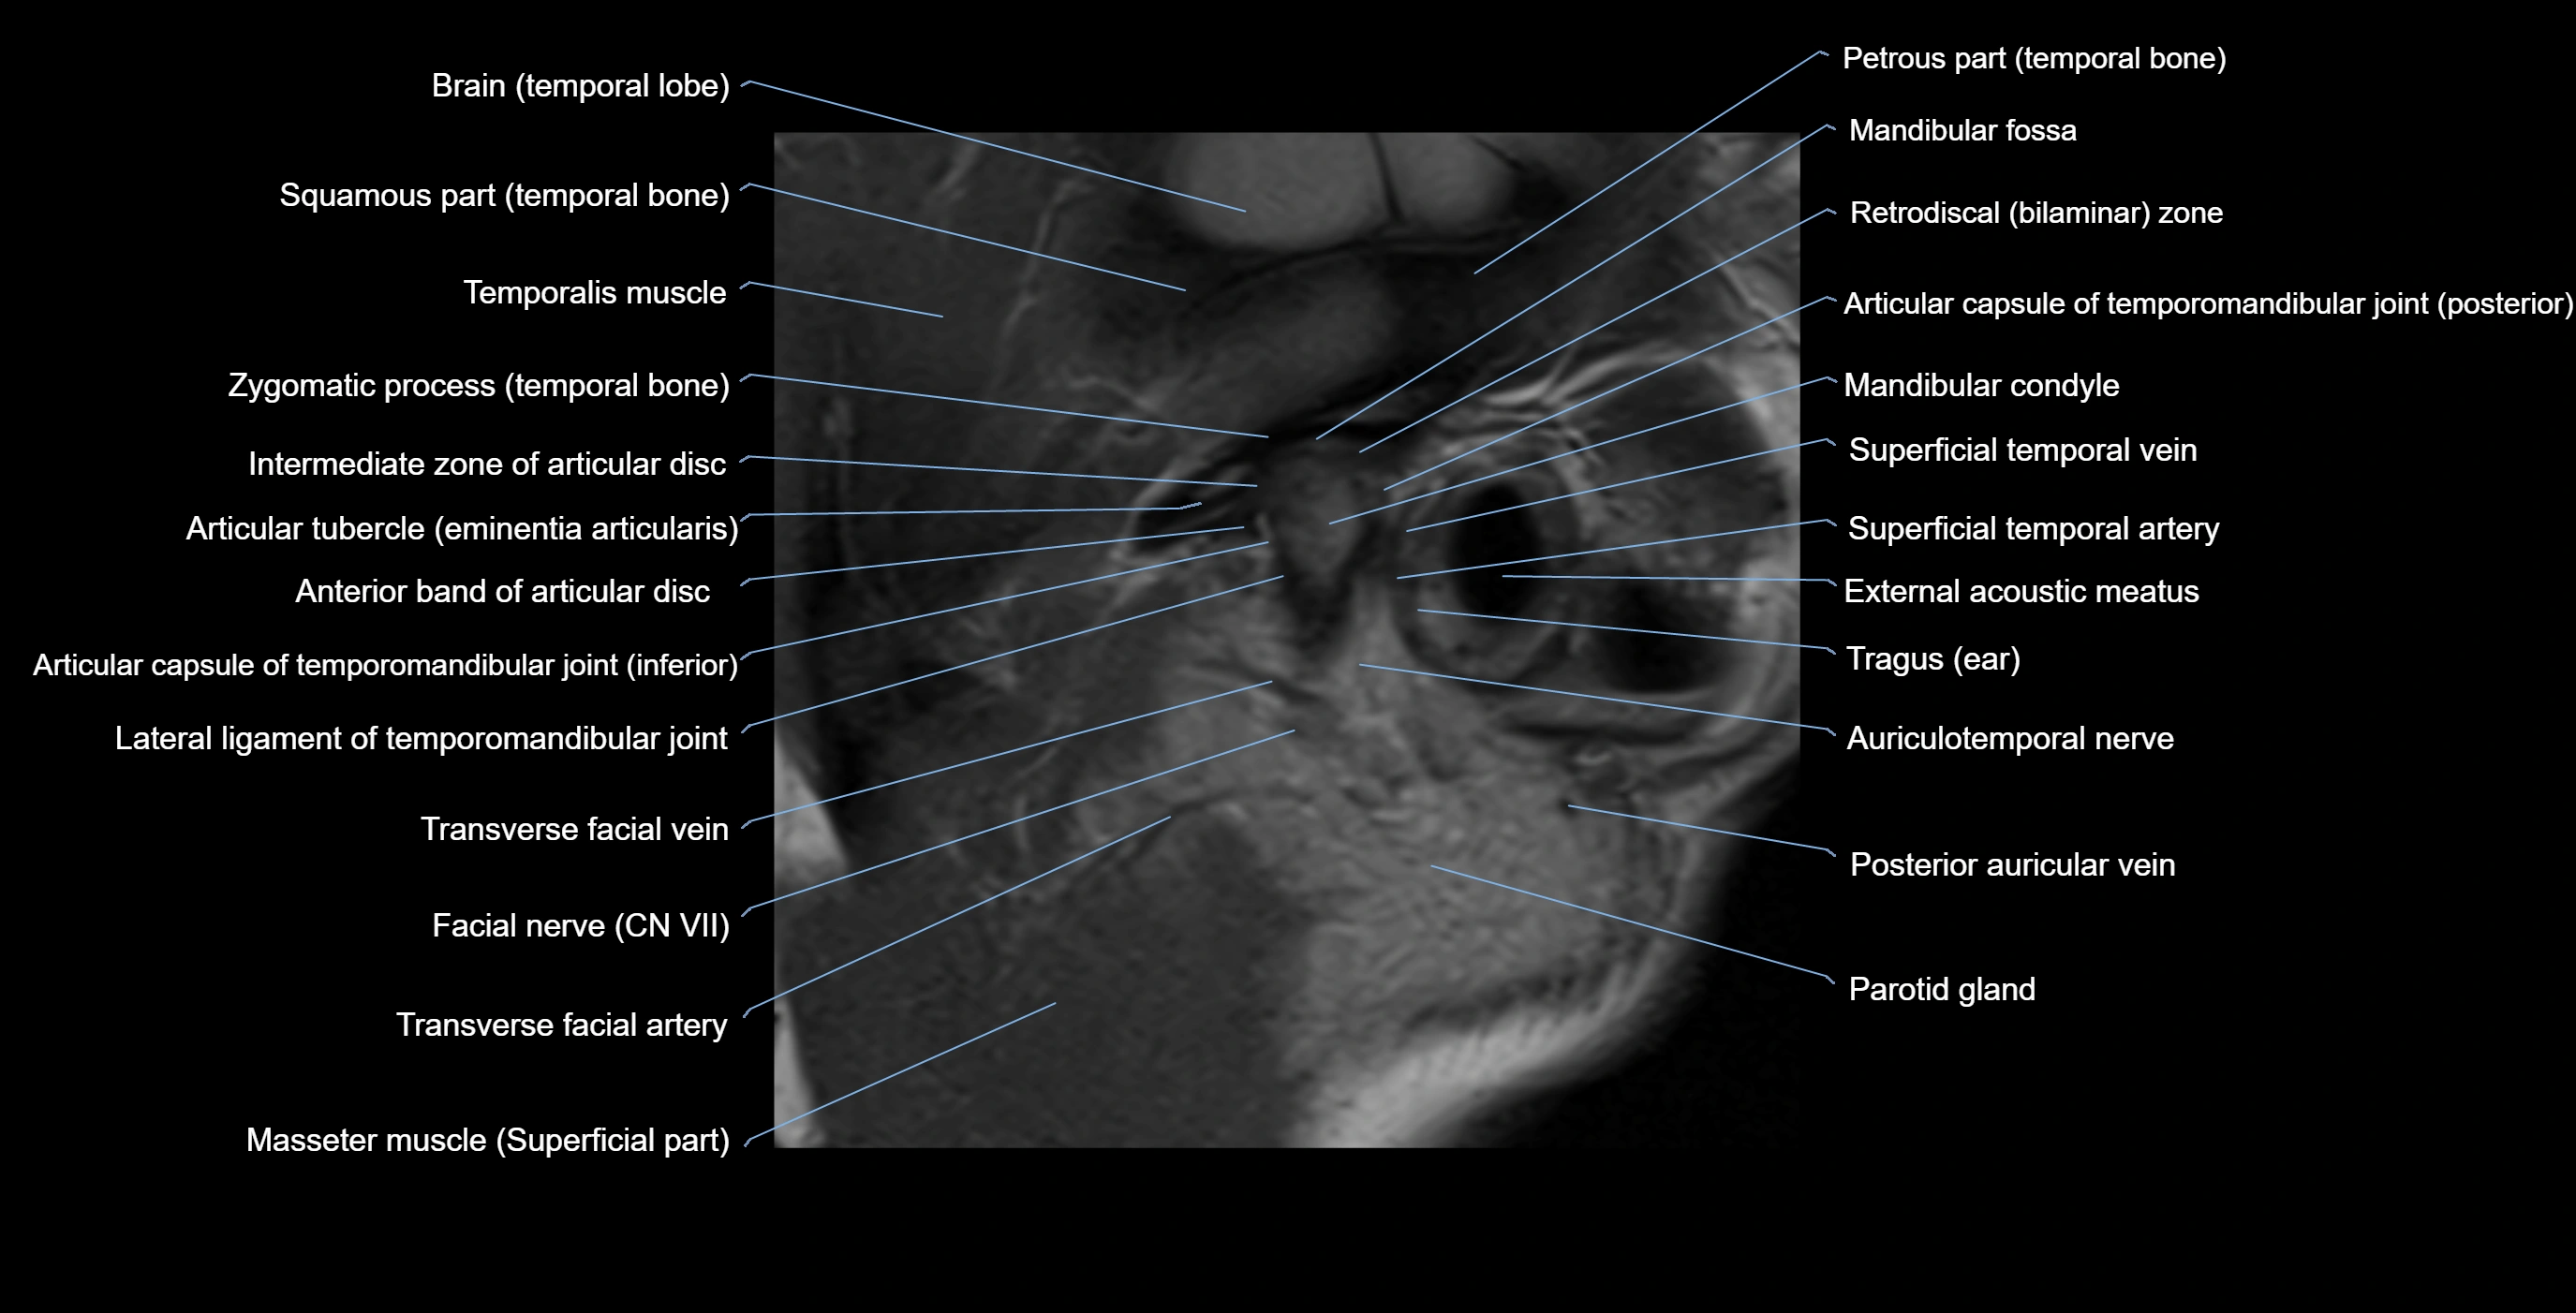

MRI appearance

T1-weighted images:

• Cortical bone: Low signal intensity

• Cancellous marrow: Intermediate to high signal depending on fatty content

• Teeth: Signal void structures

• Adjacent soft tissues: Normal gingiva and oral mucosa signal

T2-weighted images:

• Cortical bone and teeth: Low signal

• Marrow: Intermediate signal